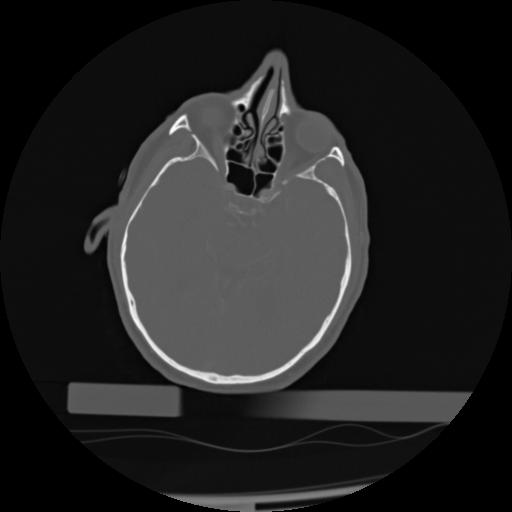

21 ANGIO,CE,Axial,3.0,ANGIO,,